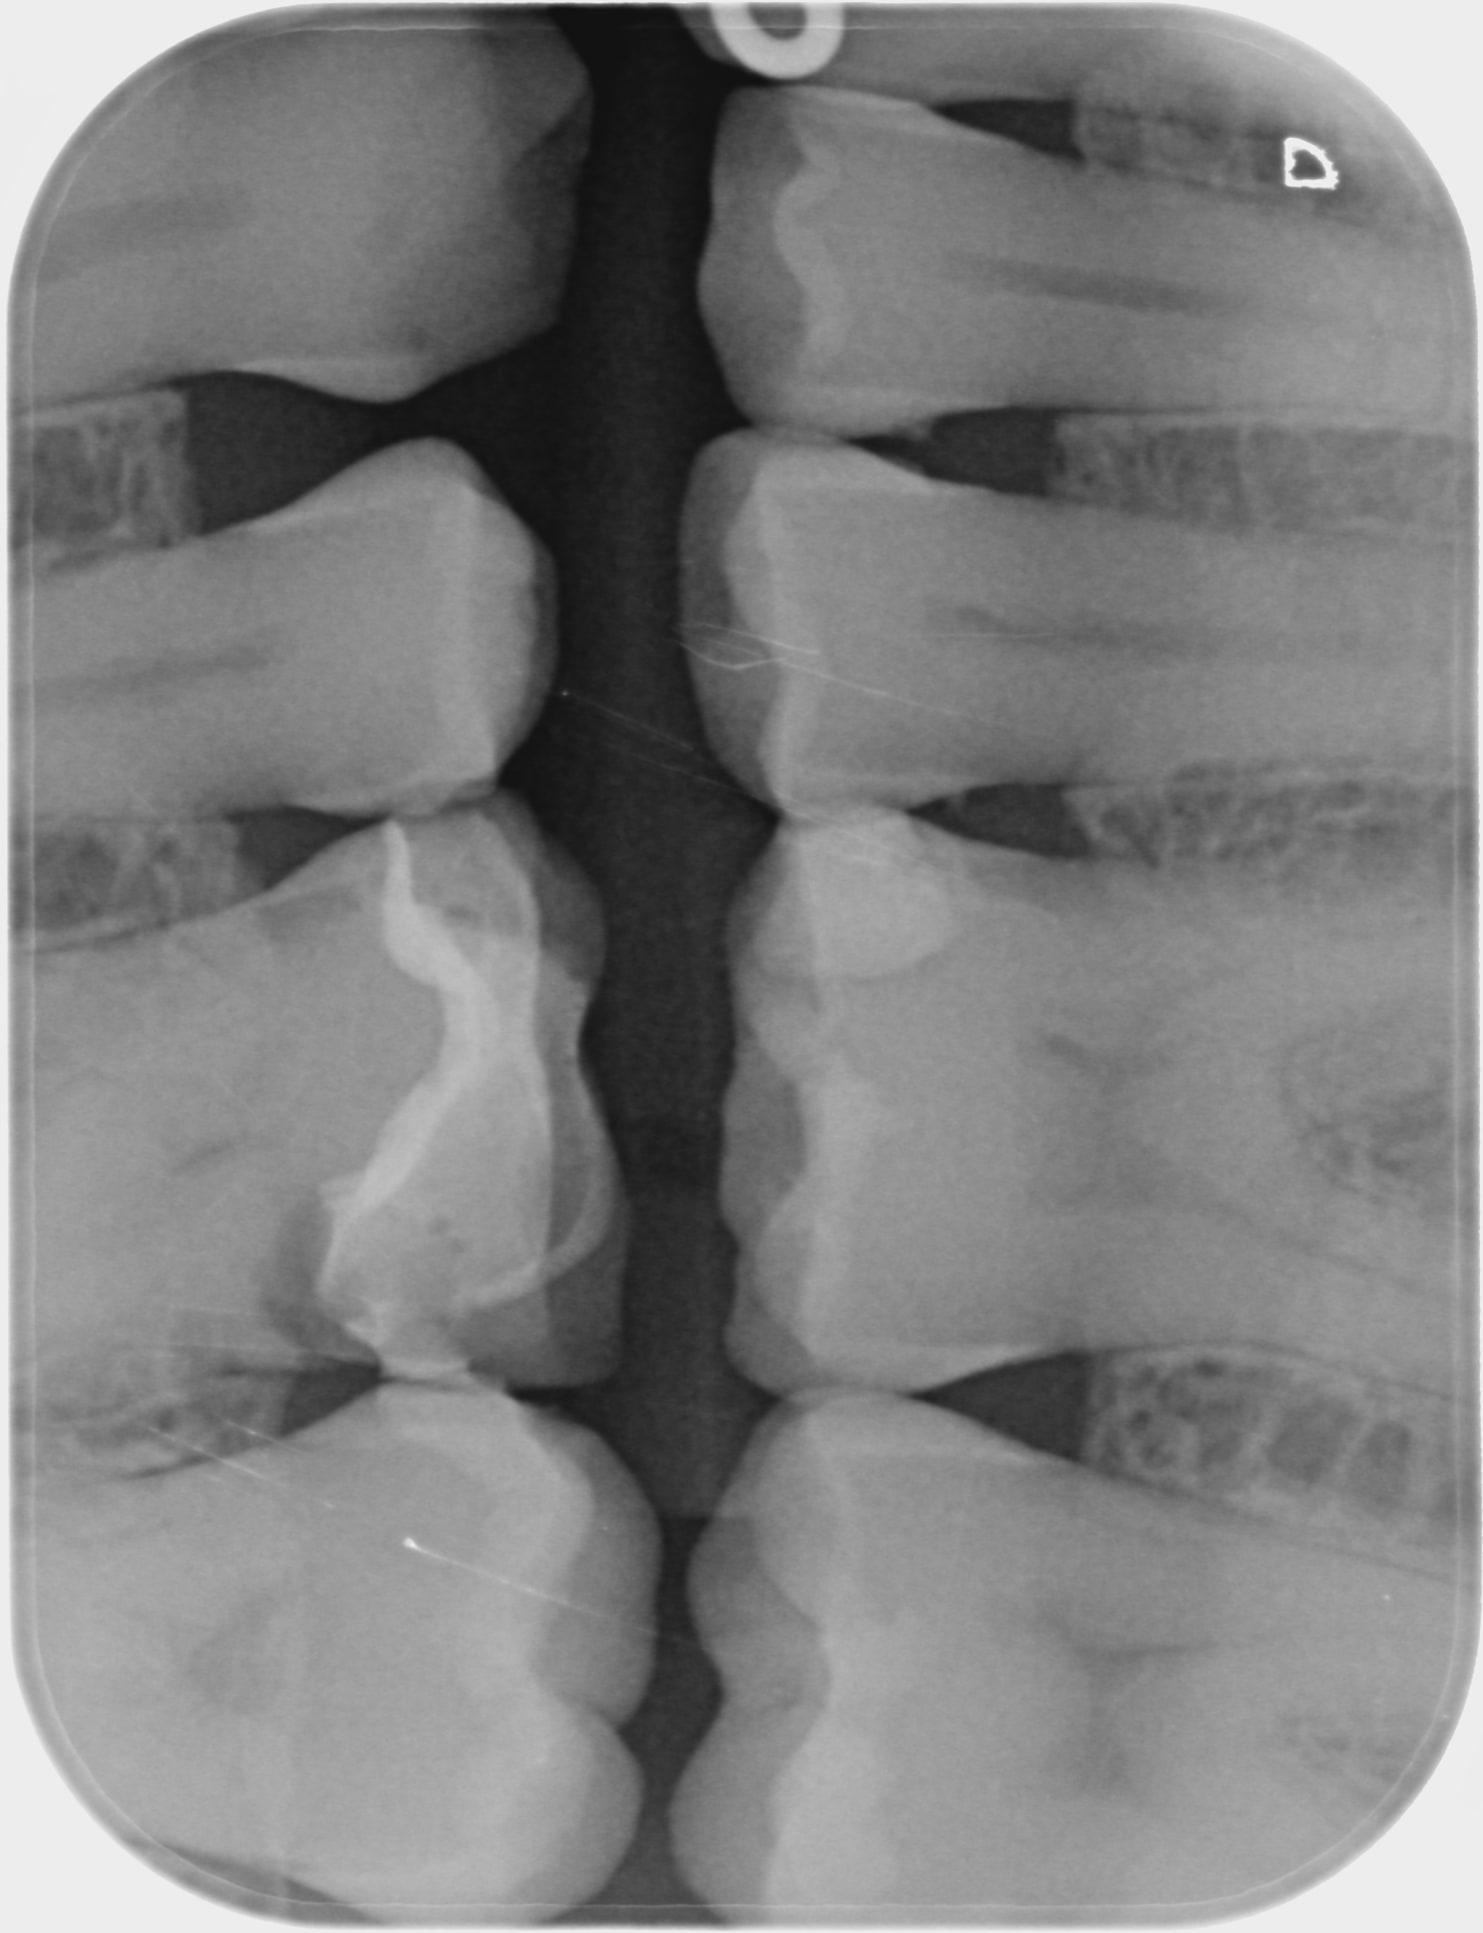

C'était le mv2 que je n'avais pas trouvé et qui s'était infecté.

Par contre, j espère que tu as une radio per OP crampon en place... Sinon c est une faute. Et la c est une autre histoire.

OP a mis la digue mais se disant que avec reciproc et localisateur d'apex il n'avait pas besoin de radio per op.